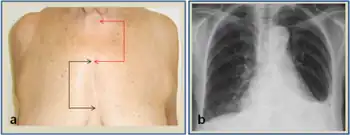

Median sternotomy is a type of surgical procedure in which a vertical inline incision is made along the sternum, after which the sternum itself is divided using a sternal saw.[1] This procedure provides access to the heart and lungs for surgical procedures such as heart transplant, lung transplant, corrective surgery for congenital heart defects, or coronary artery bypass surgery.[2][3][4]